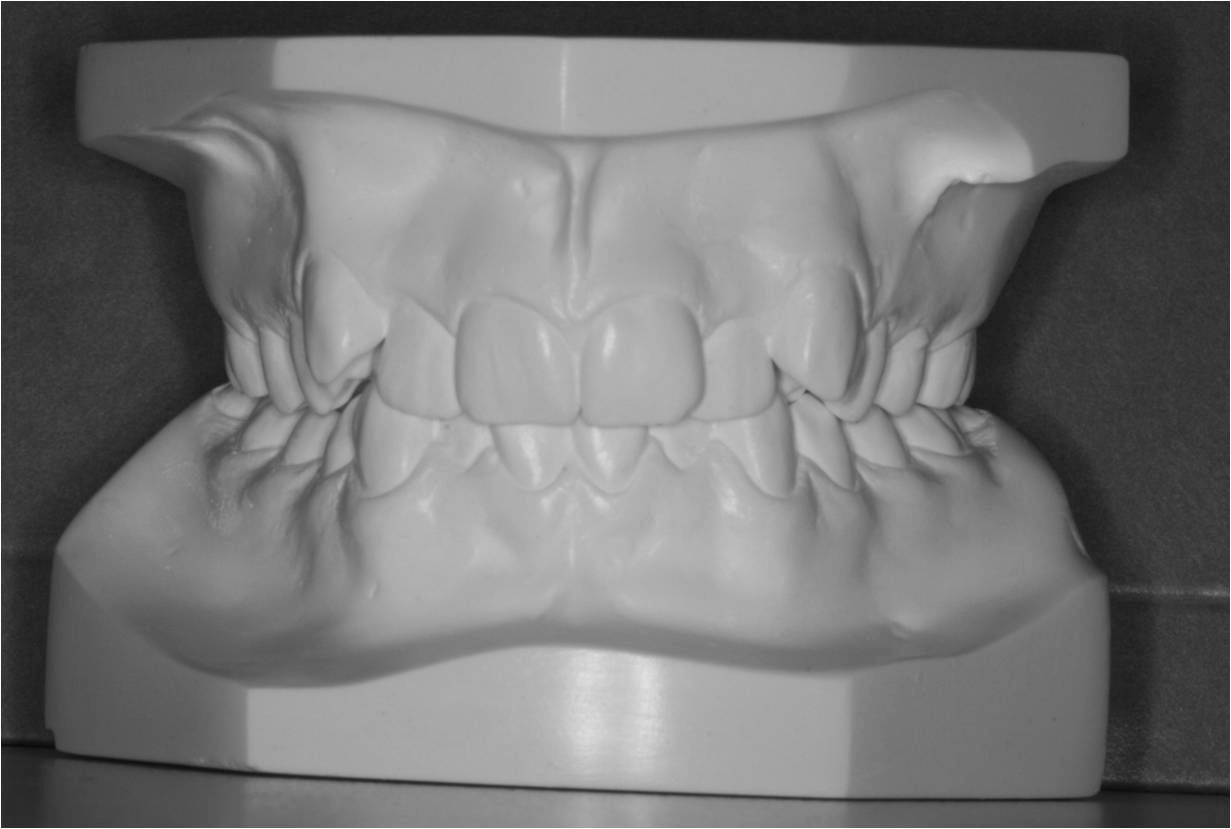

Første gang dit barn besøger Tandreguleringsklinikken, bliver der lavet studiemateriale.

Studiemateriale, består af modeller, fotos og røntgenbilleder af tænder og ansigt. Der bliver også udleveret et helbredsskema, som skal udfyldes på stedet. Det er vigtigt at vide, om jeres barn er sundt og raskt, eller om der er særlige hensyn, vi skal tage - eksempelvis til medicin med videre.